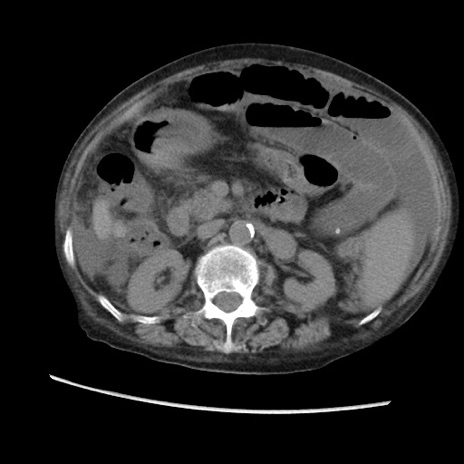

症例31(横断像)

【症例】80歳代 女性

【主訴】腹部膨満感

【現病歴】他院にて肝硬変にてフォロー中。1週間前から便秘、腹部膨満感、臍部腫瘤あり受診となる。

【既往歴】肝硬変

【身体所見】腹部膨隆あり、皮膚変化なし、疼痛なし。

【データ】WBC 4600、CRP 0.25